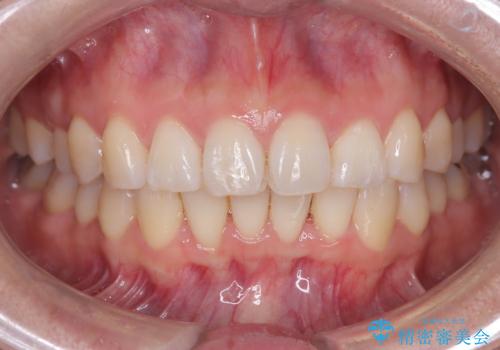

- 「歯のガタつきが気になる」「前歯の真ん中がずれている」との主訴で来院されました。診察の結果、上下の歯列に中等度の叢生(凸凹)があり、特に前歯の位置のずれ(正中の偏位)が目立つ状態でした。見た目だけでなく、かみ合わせにも影響を与える可能性があるため、全体的なバランスの改善が必要と診断しました。

治療はインビザラインを使用し、1~2週間ごとに新しいマウスピースに交換しながら段階的に歯を移動させていきました。特に上下の正中が揃うよう、奥歯や前歯の位置関係に注意を払いながら細かく設計を調整。途中の確認でも、左右のバランスが取れてきたことをご本人も実感されていました。

治療期間は約1年半で、ガタついていた歯列はきれいに整い、上下の前歯の真ん中もぴったりと揃えることができました。透明なマウスピースのため周囲に気づかれず治療が進み、快適に続けられたとの感想もいただいています。